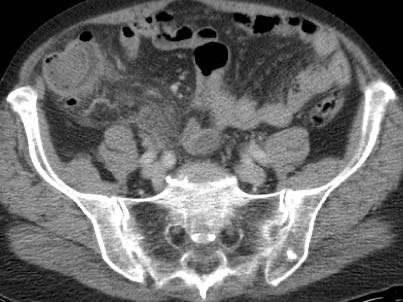

Ở người phụ nữ 56 tuổi này với CRP 180, siêu âm phát hiện dịch trong phúc mạc đục (*) và có thể thấy ruột thừa viêm với sỏi phân (mũi tên).

CT xác nhận hai sỏi phân ở hố chậu phải với hình ảnh khí bất thường, nghi ngờ viêm ruột thừa thủng.

Chọc hút dưới hướng dẫn siêu âm xác nhận dịch mủ.

Phẫu thuật cấp cứu phát hiện viêm ruột thừa thủng với nhiễm bẩn mủ bốn góc phần tư ổ bụng.